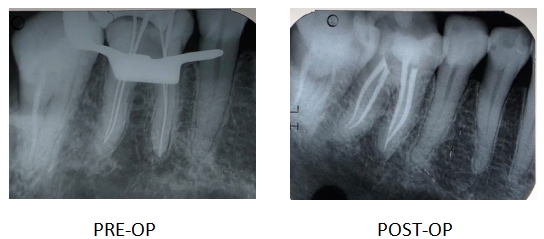

Caso Clínico 1 | Endodoncia en pieza 3.6

Paciente acudió con sintomatología compatible con pulpitis irreversible en el molar inferior izquierdo (3.6). Se decidió realizar tratamiento endodóntico bajo aislamiento absoluto, respetando todos los p rotocolos de desinfección.

Se realizó la preparación biomecánica utilizando el sistema de limas R-Shaper de Rogin, que permitió una conformación eficiente y segura de los conductos, respetando la anatomía radicular y facilitando una irrigación efectiva.

En la imagen postoperatoria se observa una obturación tridimensional adecuada, con buen manejo de la longitud de trabajo, densidad y conicidad. Se utilizó técnica de condensación lateral y sellador biocerámico.

Este tipo de resultados reflejan la importancia del diagnóstico preciso, la tecnología rotatoria adecuada y la dedicación clínica.